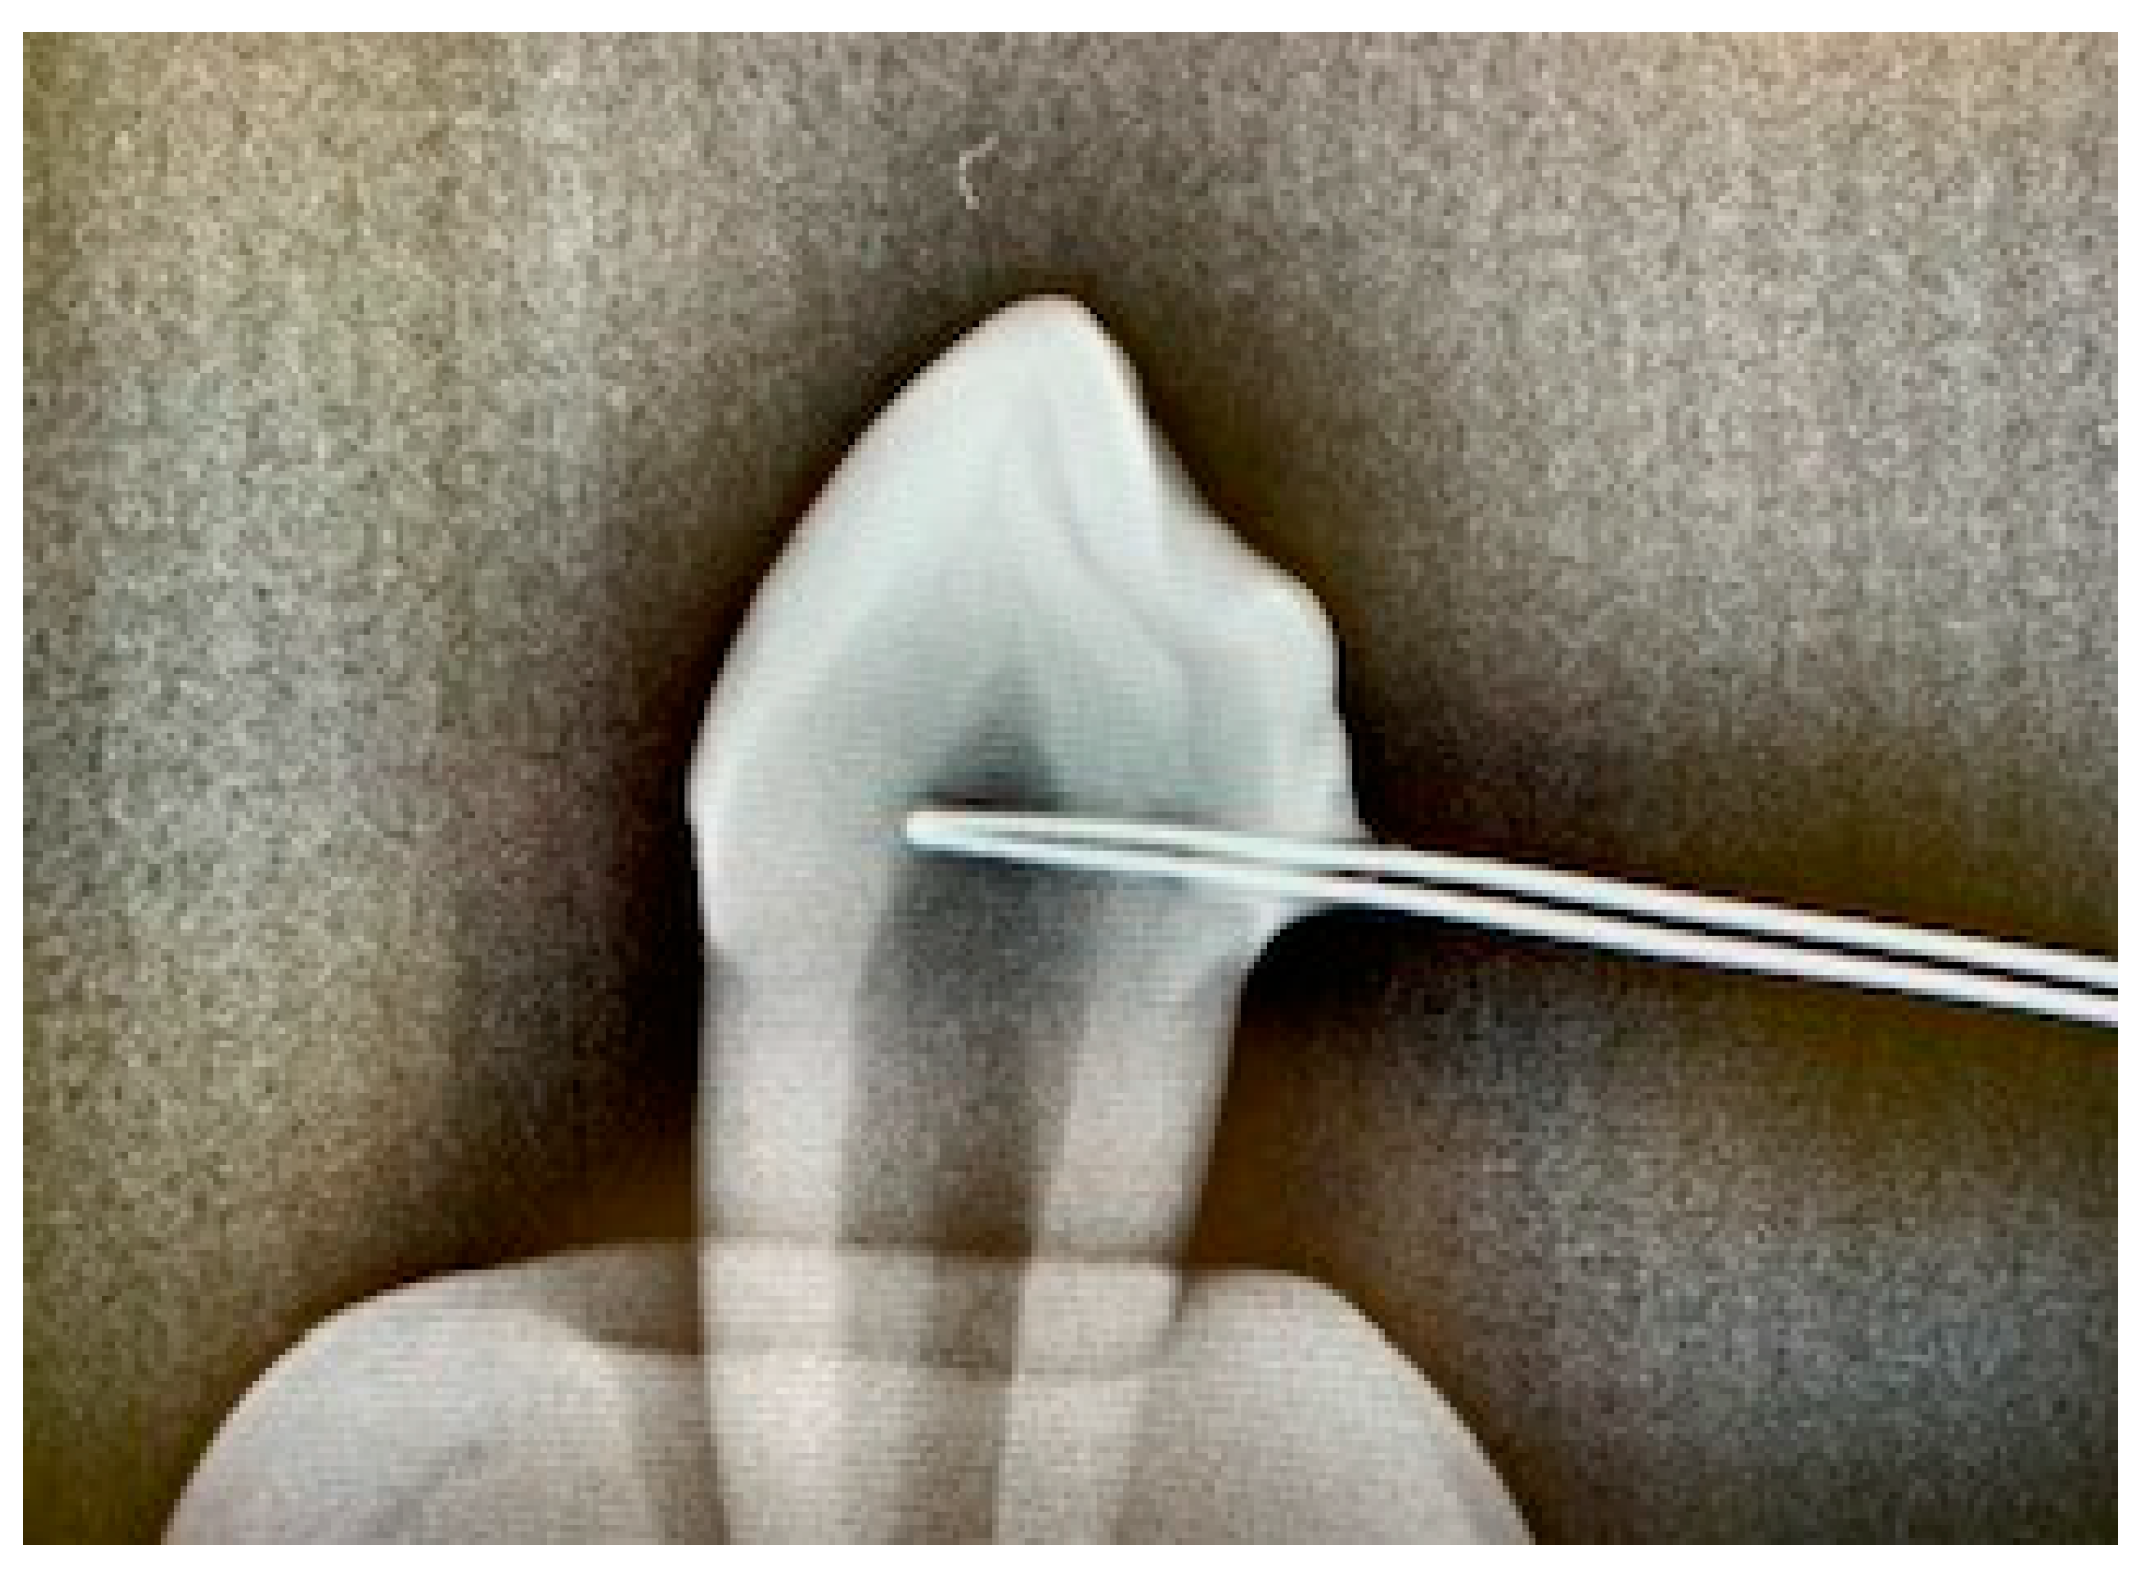

2. Materials and Methods

- Group 3 (test): diode laser EzLase 940 nm 2 W, single fiber 300 µm (EzTip E3–9 mm, BIOLASE, Inc.), bleaching gel (Laserwhite*20), irradiation time 30 s, repeat irradiation, resting time 15 min, distance between tooth and laser approx. 1.5–2.0 cm, spot size on tooth: 154–255 mm², and 47–78 J/cm2 per tooth (two cycles).

- Group 4 (test): diode laser EzLase 940 nm 1.5 W, single fiber 300 µm, bleaching gel (Laserwhite*20), irradiation time 30 s, repeat irradiation, resting time 15 min, distance between tooth and laser approx. 1.5–2.0 cm, spot size on tooth: 154–255 mm², and 35–58 J/cm2 per tooth (two cycles).